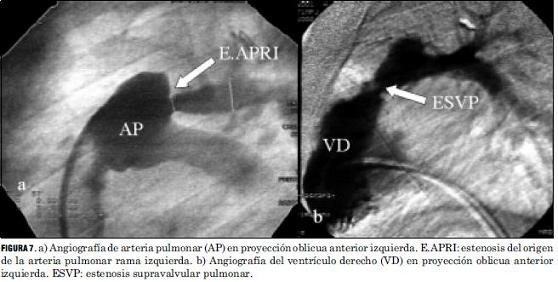

Las lesiones residuales significativas se presentaron en nueve pacientes (15%). Siete pacientes con estenosis supravalvular pulmonar, uno de ellos asociada a estenosis del origen de la arteria pulmonar rama izquierda, que requirieron angioplastia con balón (figuras 6 y 7), siendo efectiva en cuatro, mientras que en los otros tres requirió cirugía reparadora con la colocación de parche de pericardio bovino. Un paciente presentó una comunicación interauricular residual que debió ser cerrada quirúrgicamente, y otro paciente desarrolló una estenosis subaórtica (figura 8) que se resecó quirúrgicamente, todos con buena evolución (tabla 5).

La frecuencia de aparición de lesiones residuales significativas en nuestra serie fue similar a la publicada en la literatura, donde se refiere para la estenosis supravalvular pulmonar una incidencia de 5% a 30%, siendo menor su incidencia con el aumento de la experiencia del equipo. Son factores favorecedores de su aparición la corrección neonatal precoz, la existencia de un banding con larga evolución, la hipoplasia del anillo aórtico y la técnica quirúrgica empleada (16). En los casos de estenosis supravalvular pulmonar hemos tenido un porcentaje de éxito mediante la valvuloplastia con catéter balón, superior al promedio registrado en la literatura. Creemos que ello pueda deberse a múltiples variables a saber: técnica quirúrgica empleada, tamaño de muestra insuficiente para obtener conclusiones estadísticamente significativas. La aparición de una estenosis subaórtica significativa correspondió a un paciente que presentó una leve estenosis subpulmonar previo a la realización del switch arterial, subvalorada en el momento de la realización de dicha técnica.